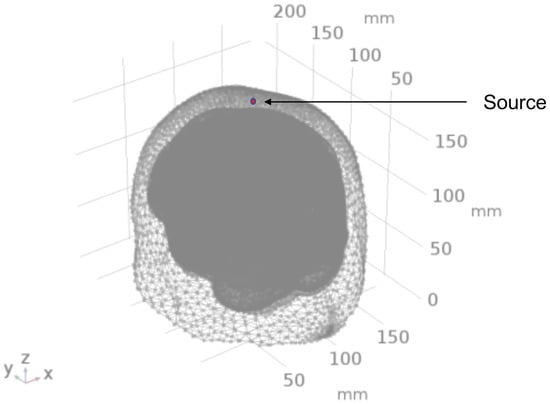

2.2. Geometry and Domain Assignment

- Domain 1: Combined scalp and skull

- Domain 2: Cerebrospinal Fluid

- Domain 3: Gray Matter

- Domain 4: White Matter